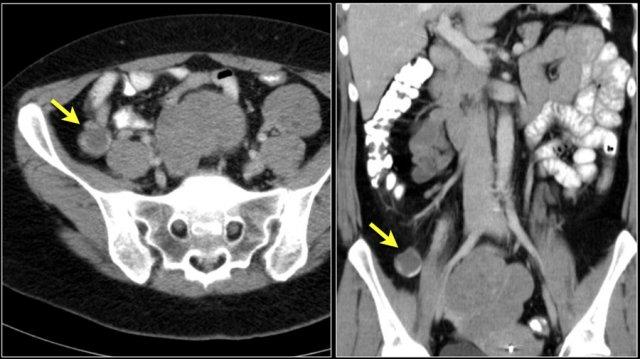

Đây là hình ảnh điển hình của u carcinoid biểu hiện là một khối mạc treo lớn với phản ứng xơ hóa desmoplastic và co kéo các quai ruột non lân cận kèm dày thành ruột (các mũi tên).

Các hình ảnh cho thấy u carcinoid biểu hiện là một khối tăng sinh mạch (mũi tên đỏ) với phản ứng xơ hóa desmoplastic (mũi tên vàng).